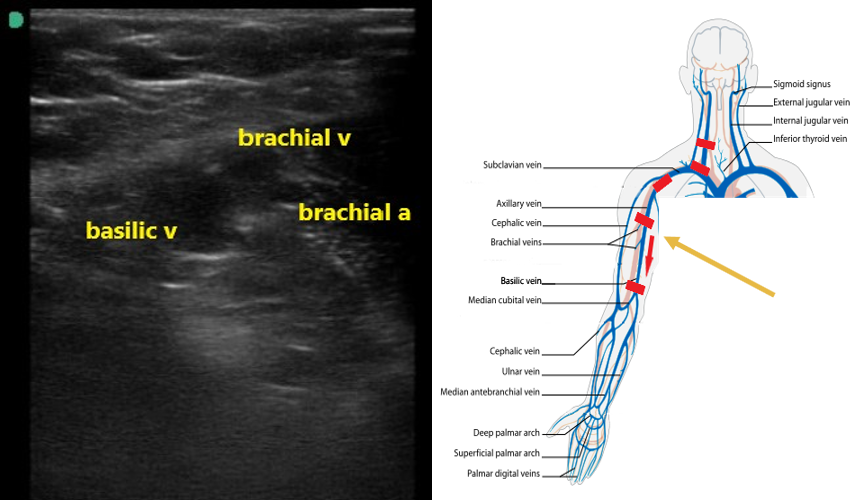

Basilic Vein Ultrasound. explain how to perform a complete duplex ultrasound exam of the. upper extremity svt can present with severe symptoms when cephalic and basilic veins are involved. learn how to scan the deep and superficial veins of the arm, including the basilic vein, using ultrasound. In order for an upper extremity venous thrombus to be considered a dvt the clot has to seen within the internal jugular (ijv), subclavian, axillary or brachial veins. The basilic vein is an ideal target for usgivs because it is. upper extremity venous doppler is performed to rule out deep vein thrombosis (dvt). Bedside ultrasound performed by a surgeon is an excellent tool that can provide immediate answers and prevent unnecessary delays in treatment. this video shows the use of ultrasound guidance to place catheters in peripheral veins in the upper extremities. the next vessel to visualize is the basilic vein which runs along the medial edge of the upper arm.

Bedside ultrasound performed by a surgeon is an excellent tool that can provide immediate answers and prevent unnecessary delays in treatment. The basilic vein is an ideal target for usgivs because it is. explain how to perform a complete duplex ultrasound exam of the. In order for an upper extremity venous thrombus to be considered a dvt the clot has to seen within the internal jugular (ijv), subclavian, axillary or brachial veins. learn how to scan the deep and superficial veins of the arm, including the basilic vein, using ultrasound. this video shows the use of ultrasound guidance to place catheters in peripheral veins in the upper extremities. upper extremity svt can present with severe symptoms when cephalic and basilic veins are involved. the next vessel to visualize is the basilic vein which runs along the medial edge of the upper arm. upper extremity venous doppler is performed to rule out deep vein thrombosis (dvt).

Basilic Vein Ultrasound The basilic vein is an ideal target for usgivs because it is. upper extremity svt can present with severe symptoms when cephalic and basilic veins are involved. upper extremity venous doppler is performed to rule out deep vein thrombosis (dvt). Bedside ultrasound performed by a surgeon is an excellent tool that can provide immediate answers and prevent unnecessary delays in treatment. In order for an upper extremity venous thrombus to be considered a dvt the clot has to seen within the internal jugular (ijv), subclavian, axillary or brachial veins. The basilic vein is an ideal target for usgivs because it is. the next vessel to visualize is the basilic vein which runs along the medial edge of the upper arm. learn how to scan the deep and superficial veins of the arm, including the basilic vein, using ultrasound. this video shows the use of ultrasound guidance to place catheters in peripheral veins in the upper extremities. explain how to perform a complete duplex ultrasound exam of the.